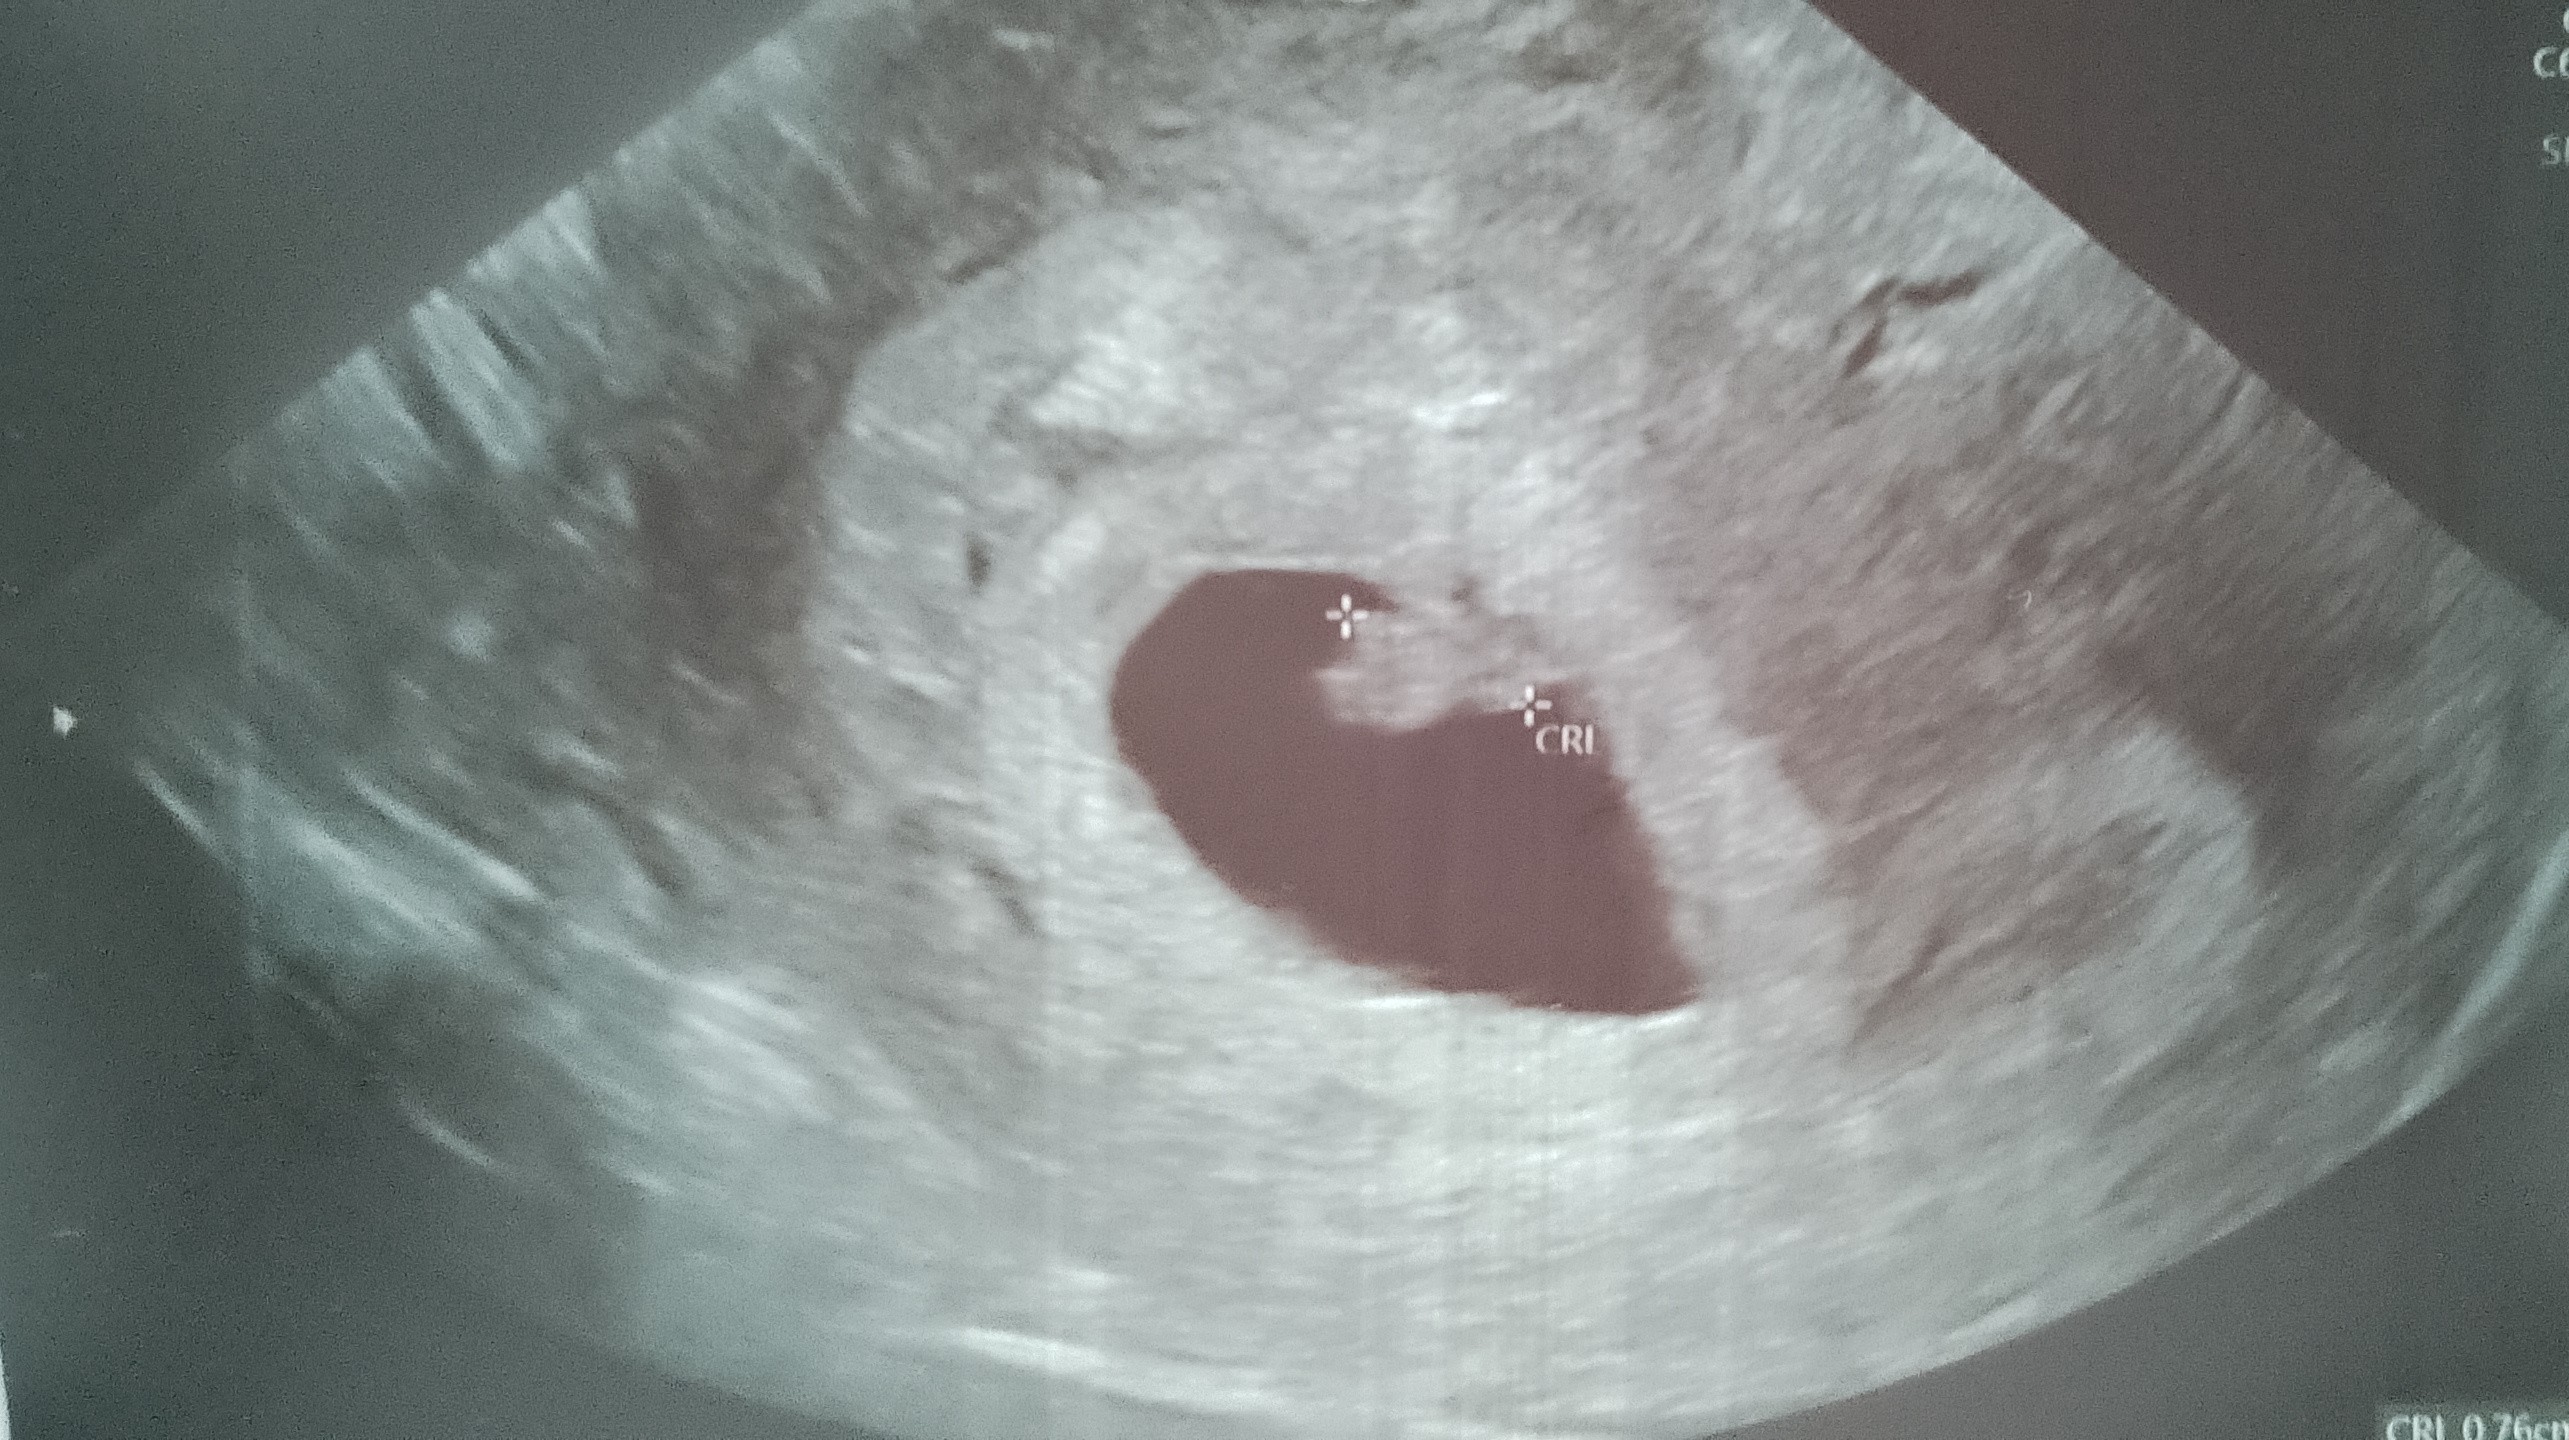

CudownieHej, melduję się po wizycie. Fasolka nadal rośnie książkowo co do dnia. Ciąża w pełni prawidłowa. Serducho bije. Całe 0,76cm małego wielkiego człowieka. Teraz szereg badań i kolejna wizyta 24.02.

Zobacz załącznik 1734313

No i bajecznie!Hej, melduję się po wizycie. Fasolka nadal rośnie książkowo co do dnia. Ciąża w pełni prawidłowa. Serducho bije. Całe 0,76cm małego wielkiego człowieka. Teraz szereg badań i kolejna wizyta 24.02.